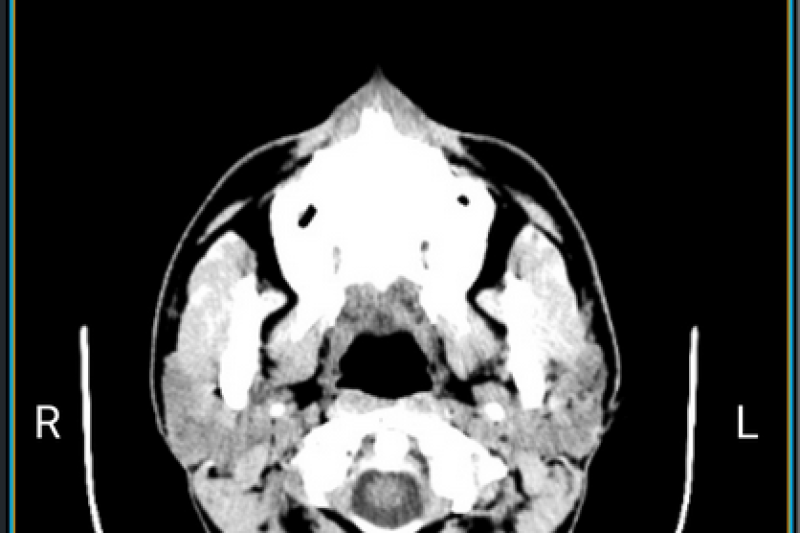

Les proves de l'Àrea de Diagnòstic per la Imatge ja estan disponibles en l'APP Taulell Virtual de Marina Salud. La petició del resultat de les exploracions d'ecografia, TAC, Ressonància Magnètica, Mamografia o Radiologia Convencional les pot realitzar qualsevol pacient, tant des dels caixers automàtics de l'hospital, com des de l'aplicació Taulell Virtual MS.